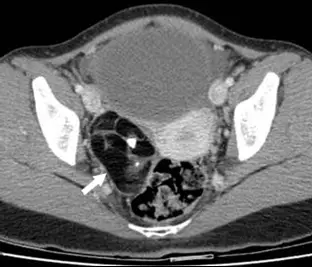

35歲女性病人主訴下腹疼痛,超音波檢查發現疑似右側卵巢腫塊,電腦斷層檢查呈現如圖,箭號所示最有可能的診斷為何?

- 檢查方式:這是一張骨盆腔的軸位(Axial)電腦斷層(CT)影像。

- 解剖位置:

- 前方可見充滿尿液的膀胱(Bladder)。

- 中央偏右側可見子宮(Uterus)。

- 病灶位置:在子宮的右側(影像左側),有一個邊界清楚的囊性腫塊(Cystic mass)。

- 病灶特徵:

- 脂肪密度(Fat attenuation):箭頭所指的區域呈現非常低密度的黑色影像。在 CT 上,這種「比肌肉黑、比水黑」,但略高於空氣(Air)的密度,是脂肪的典型表現(CT值約 -50 到 -100 HU)。

- 鈣化點(Calcification):腫塊內部或邊緣可見極高密度(白色)的亮點,這代表鈣化、牙齒或骨骼組織。

- 液平面(Fluid-fluid level):脂肪與液體混合可能形成分層,稱為脂液平面(Fat-fluid level)。

- 綜合判讀:卵巢腫瘤內同時出現「肉眼可見的脂肪(Macroscopic fat)」與「鈣化/牙齒」,是**Dermoid cyst(皮樣囊腫 / 成熟畸胎瘤)**的典型影像特徵。

本題的診斷關鍵在於箭頭所指的脂肪成分。在年輕女性(35歲)的卵巢腫塊中,發現脂肪密度(Fat density)幾乎可以確診為良性的成熟囊性畸胎瘤(Mature Cystic Teratoma),也就是俗稱的 Dermoid cyst。影像中清晰的脂肪(黑色區域)與鈣化點排除了單純囊腫、巧克力囊腫(高密度液體無脂肪)及一般的上皮性卵巢癌。